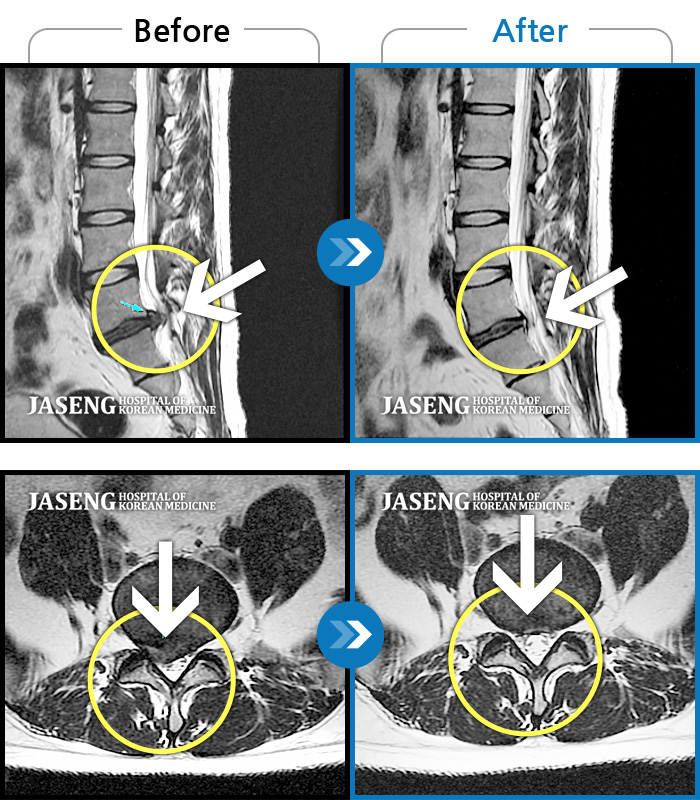

허리디스크

보라매 · 신원준 원장

우측 다리가 당겨서 걷기가 불편했다.

촬영시기

2020.04.16 ~ 2020.10.24

2020.12.04